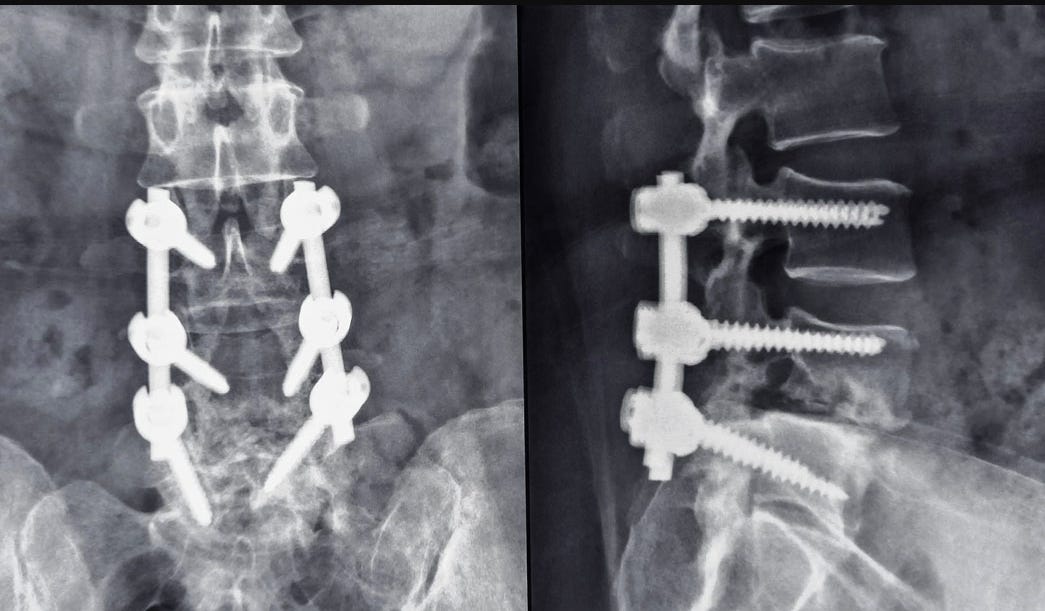

Dans le même essai mentionné ci-dessus, Levin attire l’attention sur la manière dont nos corps peuvent sembler être des machines lorsque des modifications de type transhumain leur sont apportées, par exemple lorsqu’un os cassé est réparé à l’aide de plaques métalliques et de vis. Mais ensuite, note-t-il, seul le corps sait comment se guérir lui-même, refermer l’incision.

Malheureusement, comme certains patients l’ont découvert, le corps peut déclencher une réponse immunitaire même contre des métaux supposément « inertes », comme le titane, entraînant fatigue, brouillard cérébral, maux de tête et dépression, entre autres problèmes. Si deux types de métaux sont présents dans le corps, une réaction galvanique peut provoquer une série d’autres problèmes étranges, y compris la paralysie.

Les interventions médicales ne prennent trop souvent pas en compte la complexité du corps. Il existe, après tout, des canaux sensibles régulés par des ions dans chaque cellule qui modulent l’état cellulaire, et si nous les perturbons, cela pourrait perturber les processus biologiques de manière significative. Heureusement pour les personnes dont les os doivent être réparés ou la colonne vertébrale redressée, la technologie médicale peut s’adapter aux nouvelles découvertes. Différents matériaux d’implantation peuvent remplacer le métal, tels que la céramique imprimée en 3D personnalisable ou la fibre Ossio que le corps traite et remplace par de l’os véritable.